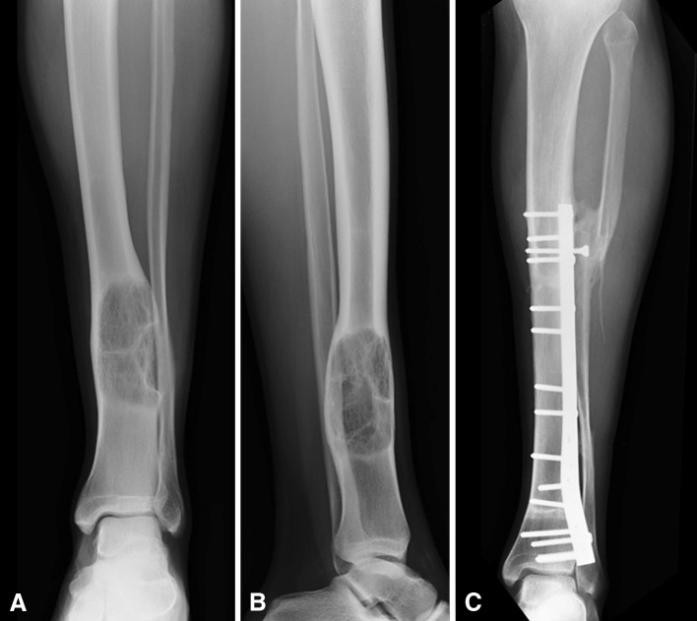

(A) AP和(B)侧位片显示 18 岁男性胫骨远端骨肉瘤的左侧胫骨和脚踝,除了截骨术和将腓骨转移到胫骨外,还接受了间隙切除和同种异体移植重建治疗。 增强同种异体移植物-宿主骨连接的愈合。(C)诊断和手术治疗35个月后,AP片显示同种异体骨完全愈合。图源:参考文献[3]